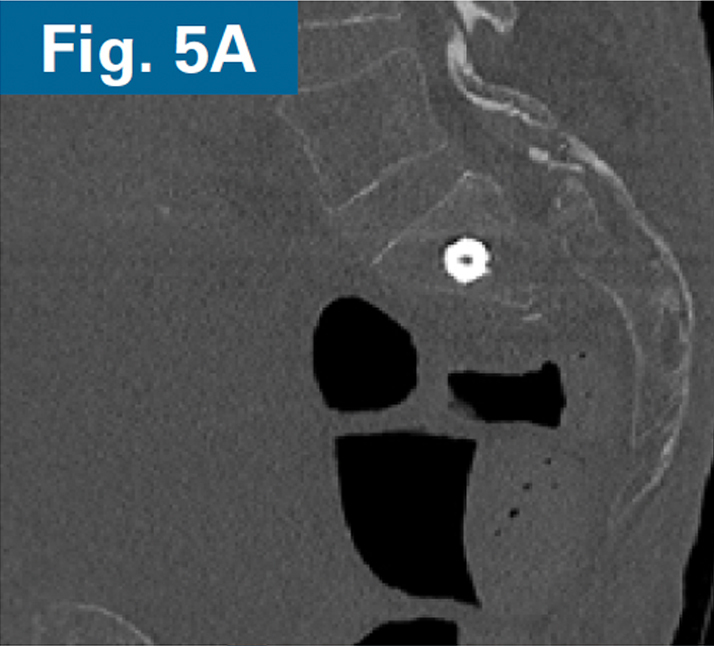

• Immediate postoperative CT scan demonstrate safe placement of implants (Figs. 5A and 5B).